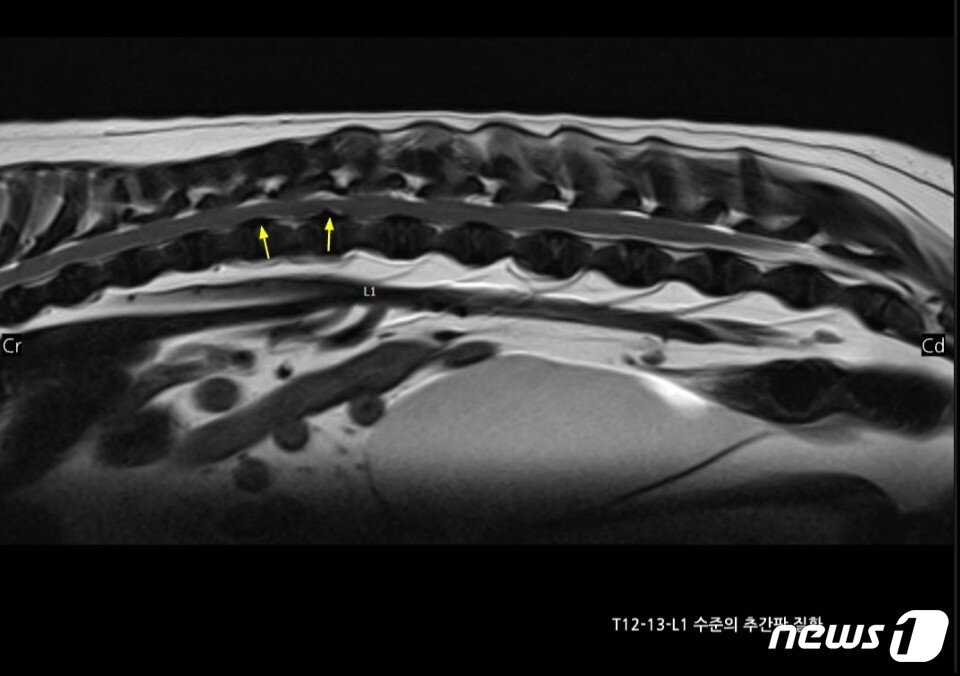

허리디스크 수술 받은 강아지. 사진 청담우리동물병원 제공 ⓒ 뉴스1